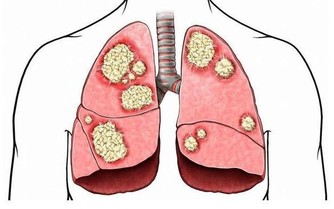

6.食物來不及消化,產生有毒物質誘發腸癌

晚餐吃得太晚,來不及完全消化,殘餘的蛋白質在腸道細菌的作用下會產生有毒的物質,又由於睡眠時腸道的蠕動很慢,使這些毒素在腸道內停留時間延長,在其長期刺激下,可誘發慢性腸炎及腸癌。

7.加速血管老化,誘發冠心病

晚飯吃得太晚,肝臟會將多餘的熱能轉變成膽固醇,致使血中膽固醇水平增高,並逐漸堆積在血管壁上,造成動脈硬化,至一定程度,就會發展成冠心病。同時,血液集中於腸胃道幫助消化吸收而使心臟供血相對不足,導致心絞痛發作。